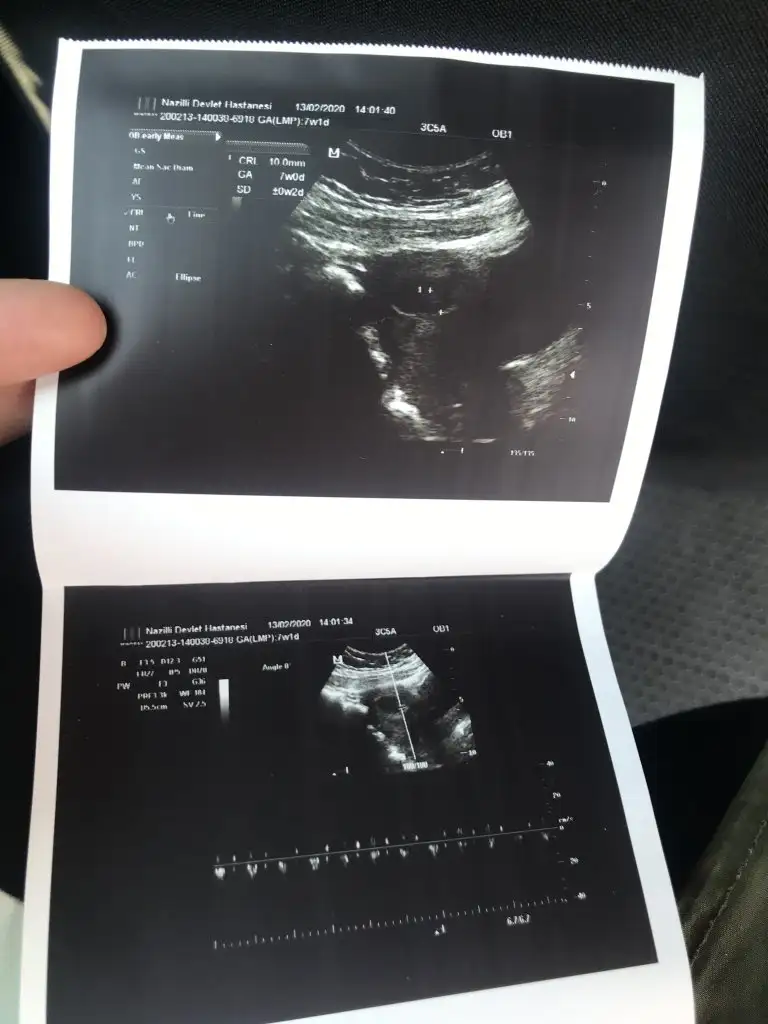

11 yada 12 hafta usg varsa bakabilirmiyim

Maalesef yok 10 haftalık ve kesenin fotoğrafı var 7 haftalık onları bi atiyim size11 yada 12 hafta usg varsa bakabilirmiyim

Bunlara göre kız sanki nette değil usg ama kese kız yönündeMaalesef yok 10 haftalık ve kesenin fotoğrafı var 7 haftalık onları bi atiyim size